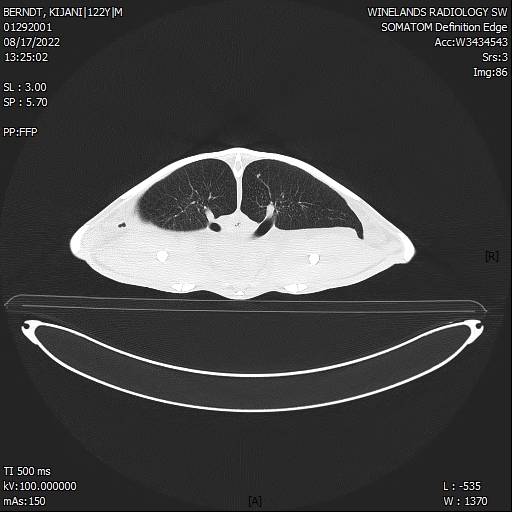

In August, CT scans of Kijani revealed that she was suffering from pneumonia, with an infected left lung. Under intensive veterinary care, Kijani successfully overcame this infection and was cleared for her “soft” release into the I&J Ocean Exhibit in late September.